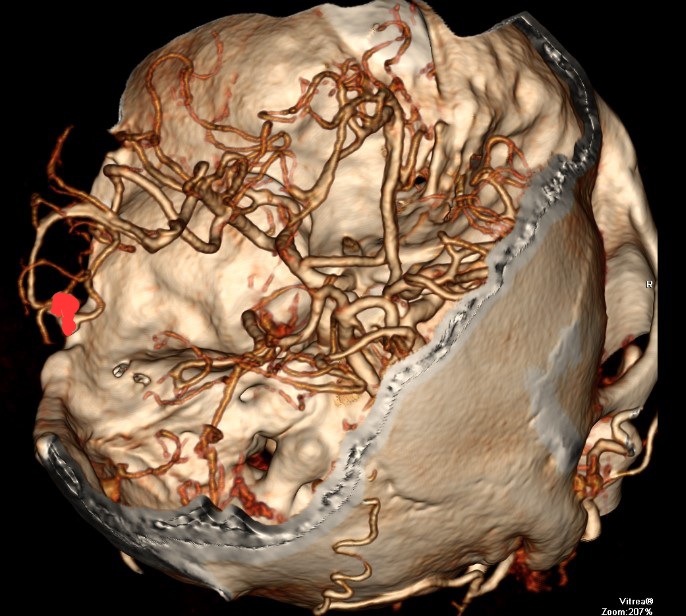

CTA显示:AVM已切除,动脉瘤夹闭良好

急诊行左颞顶大骨瓣开颅,血肿清除加去骨瓣减压,加AVM切除,动脉瘤夹闭术